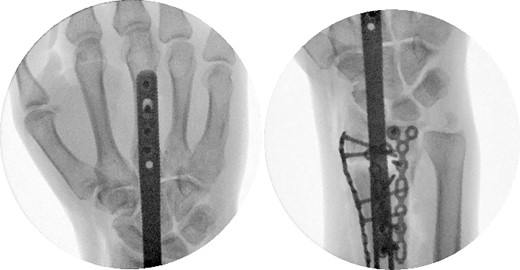

Two weeks following the procedure, the patient returned to the clinic for a follow-up visit. The wrist was swollen and ROM was limited. Hand motor functions and neurovascular exam were fully intact. Radiographs taken in clinic showed intact hardware with healing fracture. At 2 months follow-up, radiographs showed intact hardware with interval bone bridging across fracture sites. Radiographic parameters including articular alignment, radial height, radial inclination, and volar tilt were in acceptable ranges (Fig. 5). The patient reported no concerns or complications. A computed tomography (CT) scan was obtained at 10 weeks after the procedure and confirmed adequate bony healing and alignment without failure (Fig. 6). The dorsal spanning plate was eventually removed 1 month later and 4 months since the initial operation (Fig. 7).

Dorsal spanning plate hardware removal at 4 months with a PA view.

The patient followed-up in clinic 1 week after hardware removal. Clinically, the patient had no complaints. ROM was limited with both flexion/extension and supination/pronation. A QuickDASH assessment was obtained with a score of 25 out of 100, equating to minimal functional disability overall. Specifically, the patient reported moderate difficulty with washing his back and manual labor, and severe difficulty with impact recreational activities. The patient was to return to clinic in 4–6 weeks after undergoing physical therapy /occupational therapy to reassess ROM and functionality; unfortunately, the patient was lost to follow-up.

Furthermore, even though retrieval of the dorsal spanning plate did not occur until 4 months after the procedure, our patient’s CT demonstrated adequate fracture consolidation, alignment, and readiness for hardware removal by the 10-week mark. Traditionally, dorsal spanning plates are left in place for at least 12 weeks to ensure adequate fracture consolidation [6, 7]. It is likely that additional augmentation of the dorsal spanning plate with selective open reduction internal fixation in our case may have decreased time to acceptable fracture healing for plate removal. As a result, this would theoretically result in earlier ROM and return to normal activities, potentially improving clinical outcomes. However, our case was limited in its ability to adequately assess final ROM and functional abilities due to loss to follow-up.